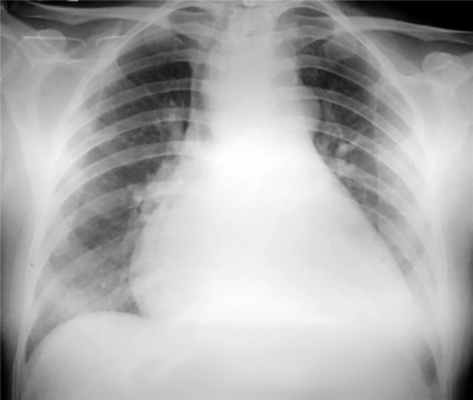

Рентгенография органов грудной клетки: легочный рисунок не изменен. Корни структурные, синусы свободные. Сердце расширено влево, верхушка удлинена и погружена в диафрагму, талия сердца сохранена. В области верхнего средостения трахея смещена вправо и кпереди, просвет сужен. Пищевод незначительно смещен вправо и кзади. Протяженность смещения органов средостения — Th2—Th5. Сужение ретрокaрдиaльного пространства 2 ст. Расширение восходящего отдела аорты, кaльцинозa клапанов не отмечено. Кардиоторакальный индекс — 64%. Новообразование верхнего средостения (рис. 2).

Рис. 2. Рентгенография органов грудной клетки. Новообразование средостения.